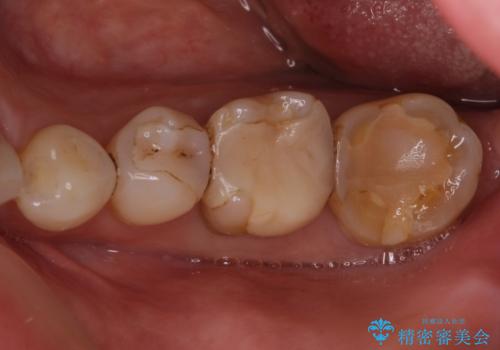

- 奥歯にものが挟まったり引っかかったりすることを気にして来院された患者様です。

詰め物と歯に隙間ができており、既に根管治療をされた歯であったため、フルジルコニアクラウンにて補綴治療をすることとしました。